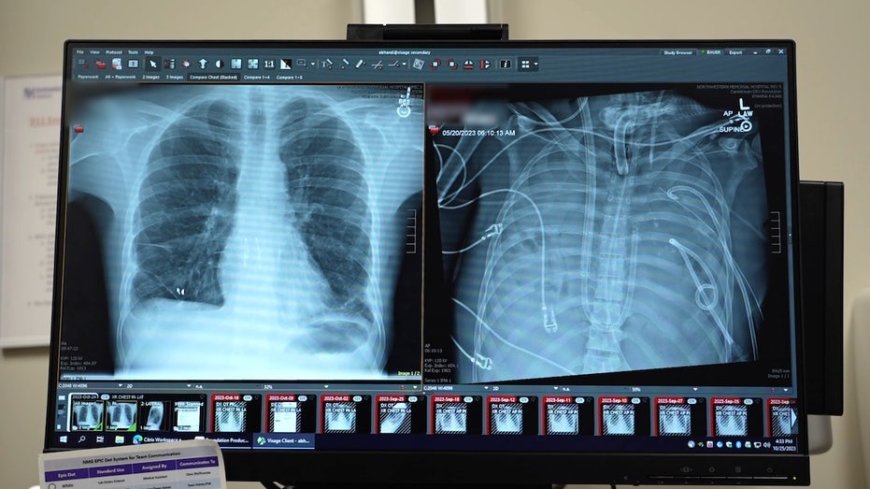

Surgeons at Northwestern Medicine in Chicago were able to keep a critically ill patient alive for 48 hours after removing both of his lungs, the hospital reported last week.

The patient, a 33-year-old Missouri resident whose name was not shared, was originally flown to Northwestern Memorial Hospital with lung failure linked to a flu infection in spring 2023.

"He had developed an infection of his lungs that just could not be treated with any antibiotics because it was resistant to everything," said Ankit Bharat, M.D., chief of thoracic surgery and executive director of the Northwestern Medicine Canning Thoracic Institute. "That infection caused his lungs to liquify and then continued to progress to the rest of his body."

The lungs needed to be removed to stop the spread of infection, but there was a dangerous risk of immediate heart failure.

In a case study, which was published last week in the Cell Press journal Med, experts revealed a "molecular analysis" of the removed lungs, showing extensive scarring and damage. This supports the idea that in some severe cases of acute respiratory distress syndrome, transplantation may be the only viable option.